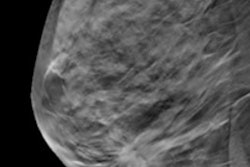

The study included data from 106,126 DBT and 221,248 2D mammography exams in 271,362 women. The exams were performed between 2010 and 2017 in 53 facilities in the Breast Cancer Surveillance Consortium (BCSC) and interpreted by 104 radiologists. Miglioretti's group compared the radiologists' screening interpretation performance one year before the adoption of DBT with their performance two years after its implementation.

Switching from 2D to 3D mammography lowered the radiologists' recall rates but didn't affect their cancer detection rates, the researchers found. These results appeared regardless of a woman's breast density.

"We found no evidence of a learning curve for the clinical interpretation of screening DBT studies," the team wrote.

Finally, the researchers also discovered that, relative to 2D mammography, the 3D recall rate of the radiologists continued to decrease as the radiologists read more DBT studies.